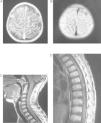

RM craneal, corte axial. Extensa afectación leptomeníngea con marcado engrosamiento y realce con contraste de toda la leptomeninge craneal que rodea tanto a los hemisferios cerebrales como a las estructuras mesencefálicas, se extiende rodeando a bulbo y médula espinal visualizada. Asimismo rodea a todos los pares craneales, incluidos el quiasma óptico y los nervios ópticos en su porción intracraneal. Engrosamiento de paquimeninge reactivo secundario a intervención de colocación de catéter DVP (A, B y C).

Niño de 12 años con episodios en los últimos 2 meses de cefalea frontotemporal, vómitos biliosos matutinos, sensación de mareo, visión borrosa y parestesias en el hemicuerpo izquierdo. Presentaba un nevus pigmentado piloso gigante en el tercio superior de espalda y la nuca de 21 x 25cm y múltiples nevus de pequeño tamaño en los glúteos, el costado y el muslo derecho, que habían sido sometidos a múltiples intervenciones de extirpación y laserterapia de CO2. La exploración neurológica fue normal, salvo papiledema bilateral más intenso en ojo derecho. La tomografía computarizada craneal fue normal. La RM craneal mostró: engrosamiento leptomeníngeo de predominio en la región frontal y parietal del hemisferio derecho, con brillo en la secuencia FLAIR e intenso realce con gadolinio (fig. 1A y B). RM medular: realce de la leptomeninge perimedular y del tronco del encéfalo (fig. 1C y D). Punción lumbar: leucocitosis (25 cel/mm3), hipoglucorraquia (0,21g/l) e hiperproteinorraquia (0,63g/l); cultivos y serologías de virus y bacterias neurotropas, y citología de células malignas negativos. A los 7 días se repitió la punción lumbar encontrándose de nuevo hipoglucorraquia (0,21g/l), hiperproteinorraquia (1,05g/l) y una hipercelularidad (23 cel/mm3) con células mononucleares atípicas y aisladas células con pigmento pardo intracitoplasmático. A los 3 meses del inicio del cuadro neurológico presentó hidrocefalia tetraventricular que precisó derivación ventriculoperitoneal. La biopsia de meninges no evidenció lesiones histopatológicas. Pasado un mes el paciente sufrió pérdida de visión del ojo derecho y crisis convulsivas consistentes en desviación de la comisura bucal e hipertonía. La RM evidenció una extensa afectación leptomeníngea, afectando también a los pares craneales, incluido el quiasma óptico y los nervios ópticos en su porción intracraneal (fig. 2). A los 8 meses del diagnóstico el paciente presentó un deterioro neurocognitivo importante, con comportamientos regresivos, disminución de la capacidad de concentración, bradipsiquia y actitud reiterativa. Dos meses después una nueva biopsia objetivó proliferación melanocítica de localización perivascular que no infiltraba parénquima cerebral. Evolucionó desfavorablemente con empeoramiento hasta situación de coma y defunción a los 11 meses del diagnóstico.